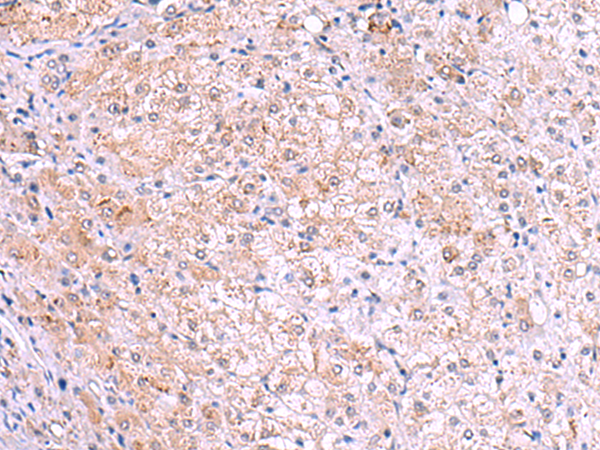

分类: 科研抗体货号: P03308别名: HYPA; FBP11; FLAF1; FNBP3; HIP10; Prp40; FBP-11; HIP-10; NY-REN-6应用: WB,IHC反应种属: Human, Mouse